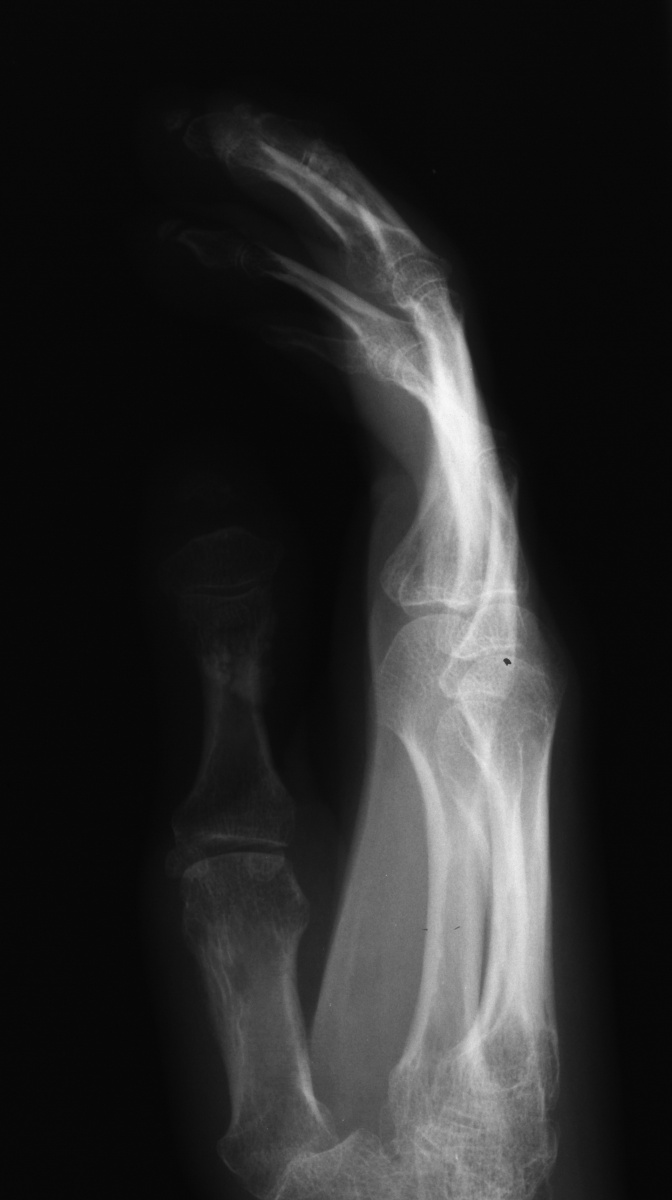

Clinical Example: Scleroderma, Calcinosis and Acroosteolysis

Scleroderma is a polymorphic condition , variably associated with a variety of conditions including joint stiffness, subcutaneous calcification and acroosteolysis. This patient with scleroderma demonstrates all of these conditions. This is most commonly associated with the finding of anticentromere antibodies.